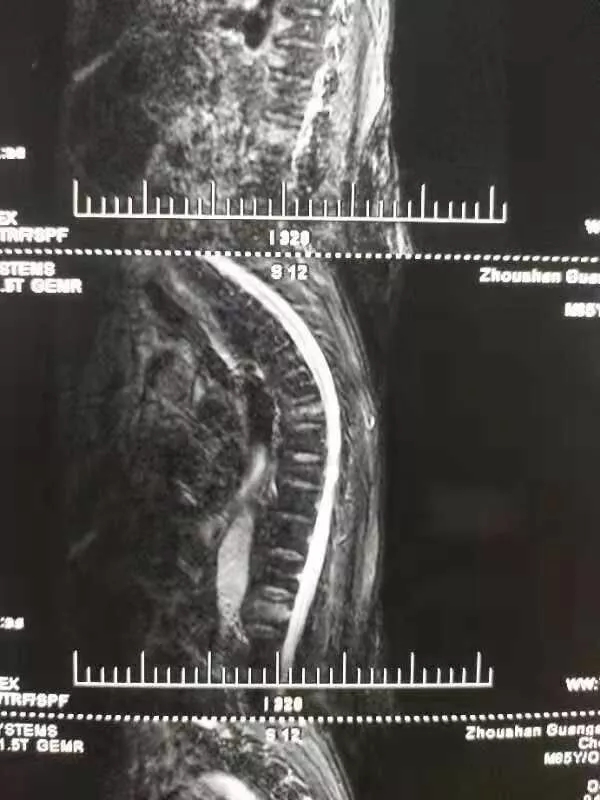

陳爺爺23日被家人送到我院門診,門診MRI、X片等檢查后,檢查結(jié)果為“腰1椎椎體壓縮性骨折”,門診在對癥處理后以“腰1椎體壓縮性骨折”將老人收入脊柱科。

進行完善的檢查,脊柱科對老人病情確診如下:胸7、腰1椎體壓縮性骨折,重度骨質(zhì)疏松癥。